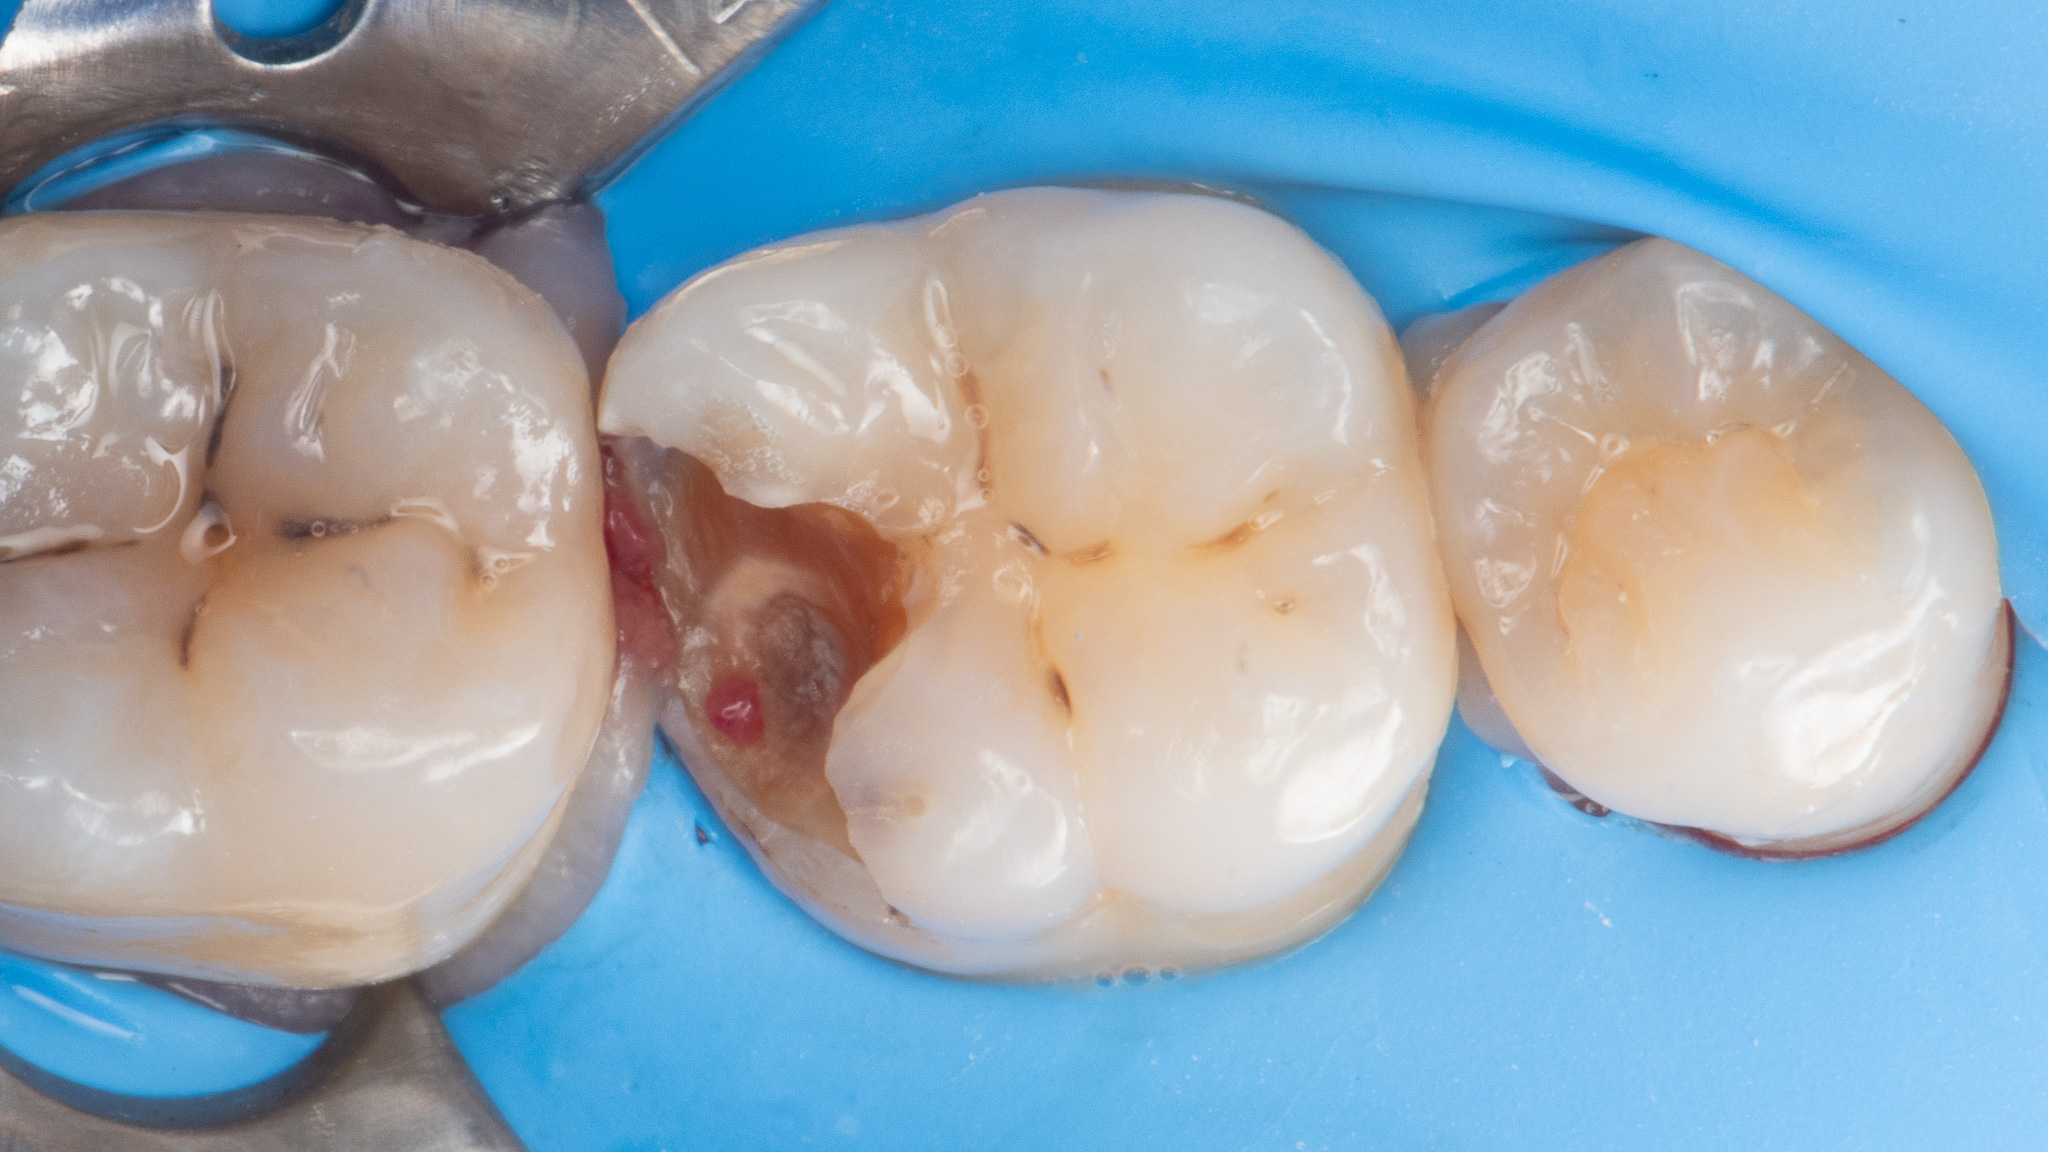

Pacjent 4

Leczenie próchnicy pierwotnej zębów bocznych (próchnica powierzchni stycznej zębów trzonowych która spowodowała odłamanie listwy brzeżnej) w zębie pierwszym trzonowym.

Odbudowa z odtworzeniem naturalnej morfologii zęba nowoczesnym materiałem światłoutwardzalnym 3M™ Filtek™ BulkFill One oraz Filtek Universal zapewniające nieporównywalną trwałość w czasie i odporność mechaniczną.

Leczenie zachowawcze odbywało się w osłonie koferdamu zapewniającej komfort pacjenta i suchość pola zabiegowego.